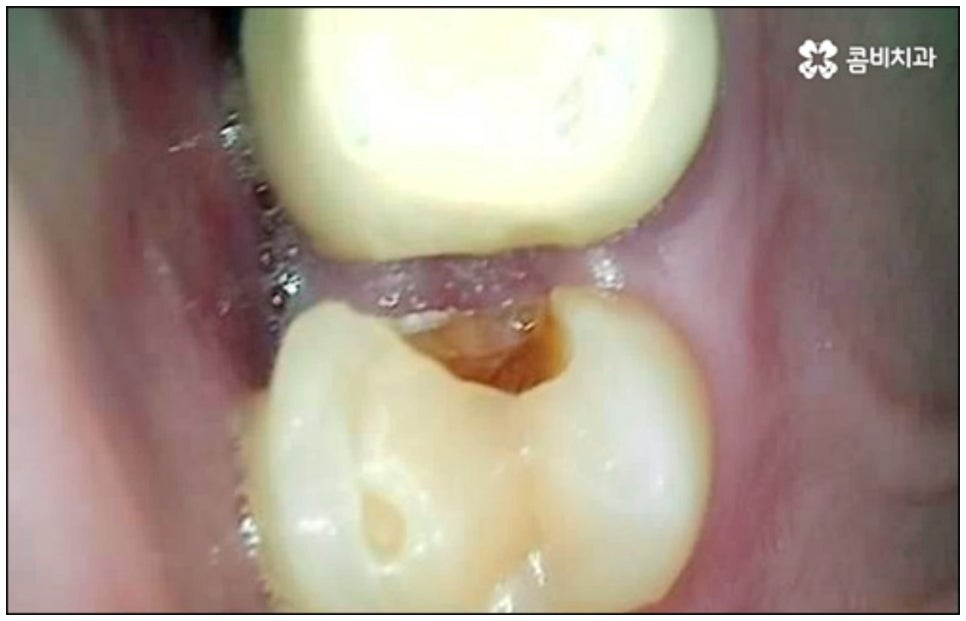

어떤 질병이라도 마찬가지이겠지만 충치나 잇몸병과 같은 구강 질환의 경우 특히 자각 증상이 있을 때 될 수 있는대로 빨리 적합한 치료를 받을 필요가 있습니다. 치아나 잇몸은 자가치유능력이 없는 데다가 시간이 지날수록 손상이 악화되는 쪽으로 속도가 빨라질 수 있어 결국 영구치를 상실하는 상황까지 이르게 될 수 있기 때문인데요, 만약 자연 치아를 잃게 되면 기본적인 저작 기능과 더불어 발음에 문제가 생길 수 있고 외모나 인상에도 좋지 않은 영향을 주게 되어 생활 속 불편함이 늘어날 수 있으니 되도록 치료 시기를 놓치지 않으시길 권유드리는 거예요.

하지만 근래 치의학이 점점 더 발달하고 임플란트 관련 기술이 진일보하면서, 발치한 당일 인공치근을 심고 임시 치아까지 장착하여 바로 씹을 수 있도록 한 당일임플란트 방법이 개발되어 전체 치료 기간을 대폭 줄일 수 있는 가능성이 높아지면서 이에 대한 문의가 많아지고 있어요. 과거에는 보통 발치 후 2~3개월 정도 기다려서 잇몸뼈가 어느 정도 회복된 다음 잇몸을 절개하고 임플란트를 식립하는 방식으로 진행을 했었다면 당일임플란트 방식은 인공 치근 주변 남는 빈 공간을 뼈이식술을 통해 바로 보강, 이후 잇몸뼈가 자연스럽게 아무는 과정에서 좀 더 빠르게 골융합이 이루어지도록 돕기 때문에 일반 임플란트 방식에 비해 기간을 단축시켜 줄 수 있는 거예요.

또한 발치 즉시 식립을 진행하게 되면 치아 상실 후 해당 부위를 오래 방치하지 않아도 되기 때문에 잇몸뼈를 가능한 그대로 유지 보존할 수 있어 수복시 보다 자연스러운 잇몸라인 형성을 기대할 수 있으며 한 번의 마취로 발치 및 식립을 한꺼번에 진행할 수 있어 환자분들의 입장에서 기간 단축 뿐 아니라 자주 치과에 내원해야 하는 불편함 및 통증에 대한 두려움을 덜 수 있다는 장점이 있어요.

다만 누구나 당일임플란트 시술이 가능한 것은 아니기 때문에 주의가 필요한데요, 위에서 언급했던 사전 치료가 필요한 경우와 같이 바탕이 되는 잇몸 건강이 좋지 않다면 바로 식립을 진행할 수 없기 때문에 시술 전 정밀 검사를 통해 꼼꼼하게 진단을 하고 각자의 상황에 대해 담당 의료진과 충분하게 상담을 해 보시는 것이 중요하다고 할 수 있습니다.